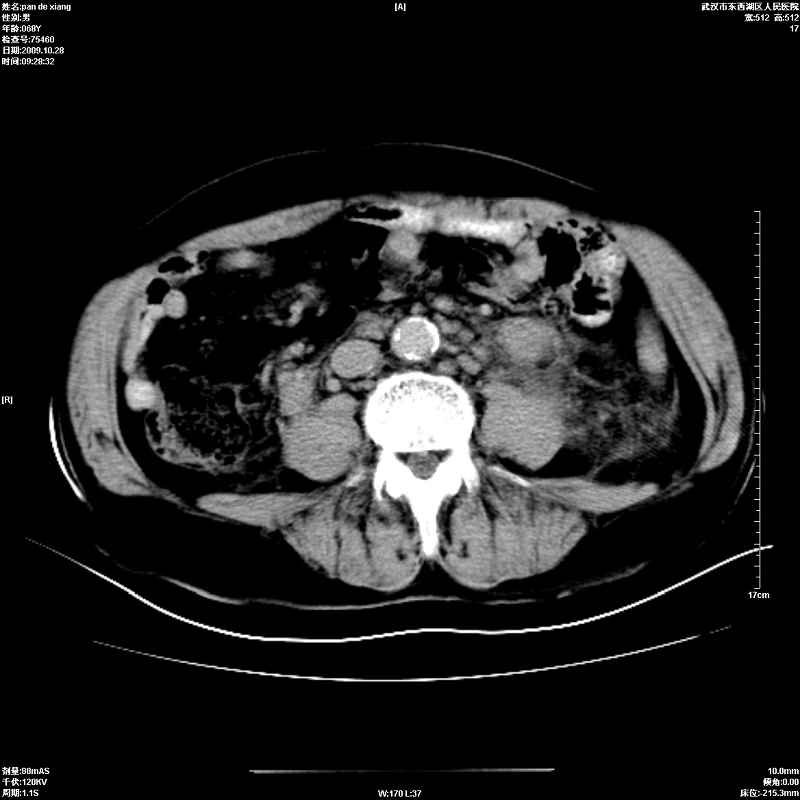

以下是引用杀毒软件在2009-10-28 20:41:00的发言:[br]结合临床考虑---白血病双肾改变或淋巴瘤。

以下是引用zxl51642在2009-10-29 9:59:00的发言:[br]结合临床“单克隆免疫球蛋白血症”,考虑双肾为继发损害并肾功能不全(尿中大量igg及少量iga、igm等大分子免疫球蛋白滤出所致继发损害),椎前软组织肿块为髓外造血。与浆细胞瘤有区别,平扫时有战友说的很清楚。